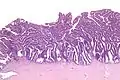

The name of the lesion describes it microscopic appearance. It has nipple-like structures with fibrovascular cores (papillae) that are long in relation to their width (villus-like), which are covered with a glandular pseudostratified columnar epithelium.

Very low magnification Intermediate magnification

Intermediate magnification Very high magnification